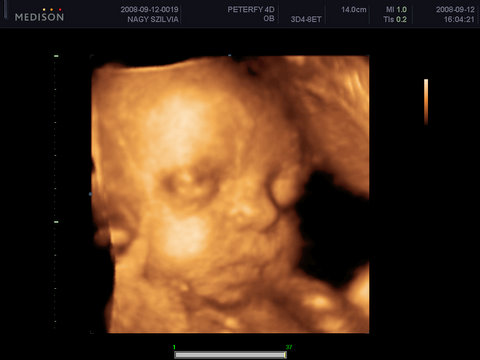

Szombaton a genesisben megneztek ot es Lalikankal minden rendben :D

Ja! A legújabb fotó a Művésznőről!